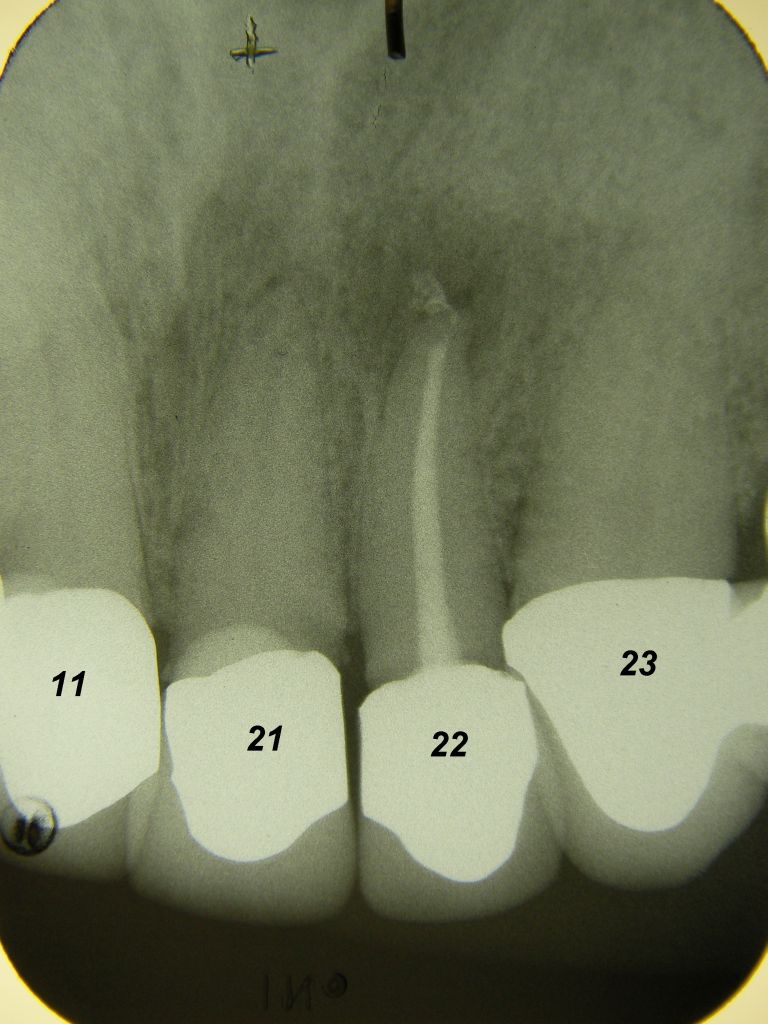

Das etwas dunkle Röntgenbild links(6/2003) zeigt diverse Probleme. Hier interessiert, daß der Zahn 22 (sprich: "zwei", "zwei") am 28.10.05 Schmerzen bereitete, weil der Zahnnerv unter Eiterbildung abgestorben war. Es brauchte 3 medikamentöse Einlagen, bis der Zahn ruhig war und am 18.11.05 eine Wurzelfüllung und einen Titanstift in den Wurzelkanal bekommen konnte. Bei der anschließenden Röntgenkontrolle rechts fiel der schlechte Randschluß der Krone 22 auf. |